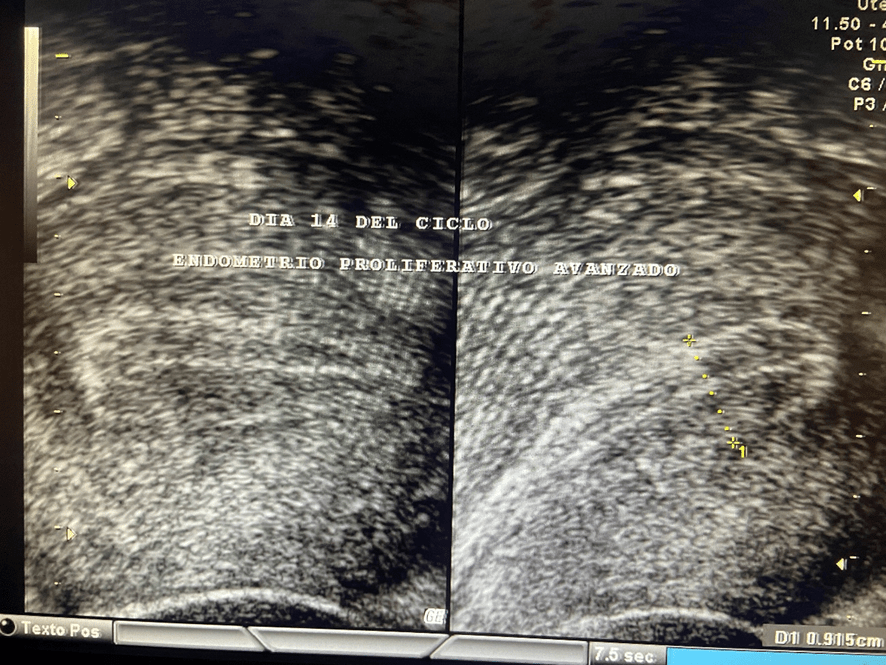

Además de estrógenos, este cuerpo lúteo empieza a segregar una hormona llamada Progesterona; la cual, es la causante de que el endometrio- que antes de la ovulación era proliferativo y con sus tres capas bien definidas- se transforme en un endometrio grueso, espeso e irregular. Se le conoce como “endometrio secretor”.